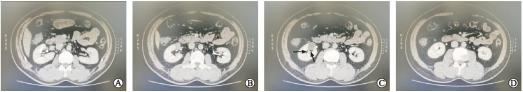

视频中的患者(详见文后大家泌尿网手术视频二维码链接)R.E.N.A.L评分为9A级,基于其较高的R.E.N.A.L评分(>7,中高危),我们决定采用RAPN术式。通过三维CT重建分析,该患者肿瘤位于右肾肾门部前唇(图1),囊实性,外突肾脏50%以上,毗邻肾动脉,手术难度较大,使用经腹腔途径RAPN是较好的选择。

A:肿瘤上极平面;B:肿瘤位于左侧肾门前唇,呈囊实性;C:如箭头所示,肿瘤边缘与肾动静脉关系密切;D:肿瘤下极平面。

图1 患者三维CT重建图